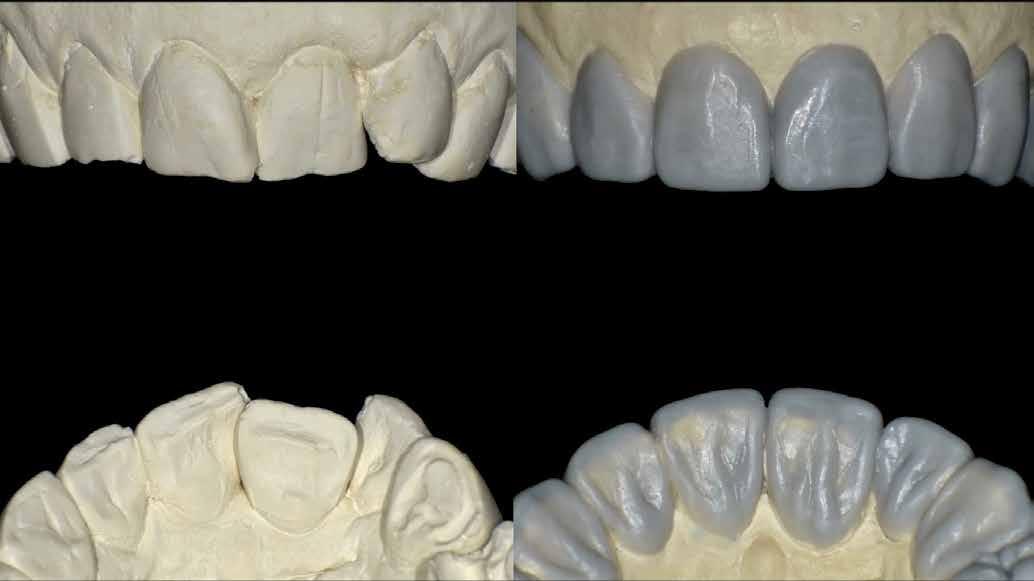

A felső és az alsó állkapocsról történt szituációs lenyomatokat kiöntötték, a laboratóriumi szkennerrel digitalizálták (3Shape), és az adatokat a Digital Denture szoftverbe importálták. A szoftver SR IvoBase® CAD és SR Vivodent® CAD Multi kombinációjával - fogszínű korongokkal - lehetővé teszi digitális protézisek automatizált gyártását.

Ideiglenes protézis CAD-konstrukcióban

Az ideiglenes fogsor elkészítéséhez a még meglévő fogakat törölni kellett a virtuális modellről (3. ábra). Ehhez a szoftver megfelelő eszközöket biztosít. A modellanalízis közben a szoftver lépésről lépésre vezet minket. Az anatómiai jellemzőket megjelöljük és a fogsor kiterjesztésének paramétereit rögzítjük (4. ábra). Az állkapocsviszony meghatározása alapján a függőlegest 5,5 mm-rel megemeltük (5. a ábra). A Digital Denture Full Arch könyvtár segítségével megtörtént a megfelelő fogforma kiválasztása (Phonares® II B71-L50-N3)

(5. b ábra)

A szoftver automatikusan előállított egy fogfelállítási mintát (6. ábra). Szükség esetén ezt individualizálhatjuk. Az alapvető paraméterek (foghossz, középvonal, harapási sík stb.) ellenőrzése után a programban „finomhangolunk", kiigazítjuk az apró részleteket és végül virtuális finírozást hajtunk végre az alaplapon és az ínykontúrokon. Mindezek elvégzéséhez a szoftvernek van eszköztára, amivel például az anyagra felvihető még több, eltávolítható belőle, illetve simítható.

Ideiglenes protézis

CAD-előállítása

Miután elmentettük a CAD-konstrukciót, a szoftver CAM-kimenetet generál a fogív és protézisalaplap kimarásához. A fogív frézelése sűrű hálószerkezetű, polikromatikus, PMMA bázisú DCL-anyagból történik (SR Vivodent CAD-Multi) (7. ábra), melynek magas a biokompatibilitása. Az anyag különlegessége a gyöngyhatás (Pearl-Structure Effect), mely kiegyensúlyozott színátmenetet biztosít. Az A1 színre esett a választás. A korong multikromatikus színátmenetének köszönhetően – él, dentin, nyakszín – a monolitikusan frézelt fogak nem igényelnek túl sok utómunkálatot ahhoz, hogy természetes hatást keltsenek. A fogsor alaplap marásához különböző ínyszínű PMMA lapokat (IvoBase CAD) integráltak a Digital Denture munkafolyamatába. A színkoncepció az IvoBase anyaggal összehangolt (Preferenc,

A CAM gép (PrograMill PM7) első lépésben nagyjából (nyers fázis) marja ki a fogíveket. Míg a fogívek okkluzálisan túlméretezetten kidolgozottak, addig az alapokat egészen pontosan a protézis alapjának megfelelően marja a gép (9. ábra) A következő lépésben lehet a fogíveket a fogsoralaphoz igazítani. Ehhez egy kétkomponensű, önkötő ragasztó áll a rendelkezésünkre (IvoBase CAD Bond), hatékony ragasztást biztosítva (9. ábra). Az ezt követő finommarás és simítás megadja a fogív és fogsoralaplap végleges formáját (10. és 11. ábra)

Az ideiglenes fogsor befejezése

A digitálisan készrevitt fogsor kidolgozásának lépéseit a minimumra csökkentették. A fogsoralaplap vesztibuláris területeinek természetes morfológiája - a konvex és konkáv területek váltakozásával - bekerült a szoftverbe, és a gép 1:1-ben megvalósította. Kívánság szerint a fogak és az íny egyedi mikrotextúrát kaphatnak. Igény és szükség szerint a kis kopások például erősítik a fogsor természetes hatását. Az előpolírozás kézidarabbal történik, mielőtt a polírgépen habkővel, univerzáis polírpasztával és pamut boffkefével a fogsor megkapja végső fényét.